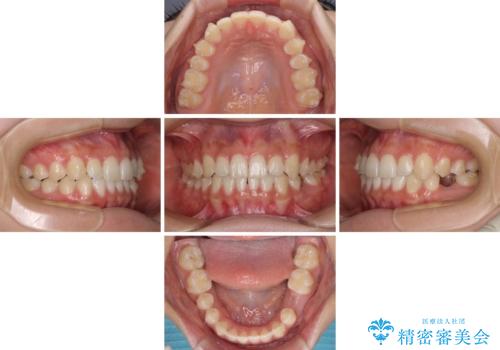

- 前歯の叢生と、奥歯の咬み合わせの悪さを気にして来院された患者様です。

左下には後続永久歯の欠損した乳歯が残存しており、叢生を相まって咬合関係が乱れていました。

乳歯は抜歯し、インビザラインにて矯正治療を行いながら、並行してインプラントによる補綴治療を行うこととしました。

矯正治療が終わるタイミングに合わせてインプラントの埋入を行っていたので、矯正治療を終了すると同時にセラミック補綴治療を行えました。

短期間でしっかりと治療を終えることができました。